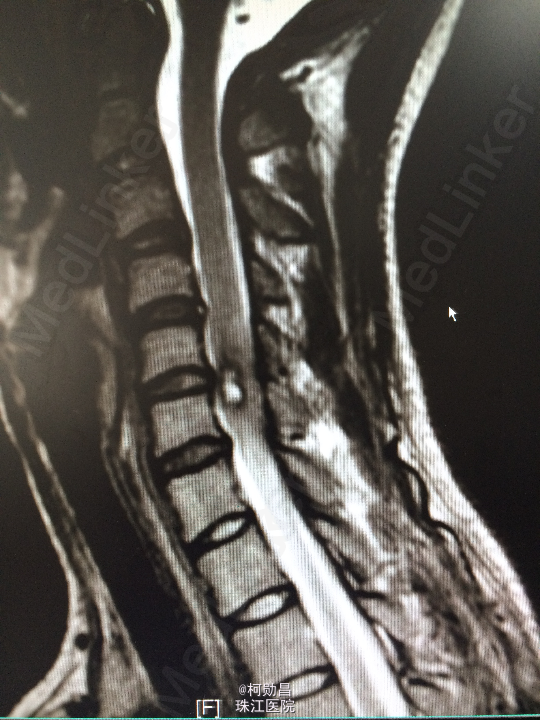

主诉:颈部疼痛伴右手麻木疼痛2月余 病史:患者缘于去年11月份无明显诱因出现右侧上肢乏力,右手小指及无名指疼痛麻木感,无头痛头晕,无间歇性跛行等,在当地医院行MR提示:颈椎椎管内占位性病变,予对症治疗后效果不佳。期间上述症状加重,遂至我院进一步诊治。

查体:颈椎下端棘突间轻压痛,颈椎活动受限,双臂丛牵拉试验阳性,压头试验阳性。四肢肌力5级,感觉:右侧前臂尺侧小指及无名指痛、触觉稍减退,余肢体及鞍区疼痛觉正常。反射:右侧肱二头肌腱反射亢进,左侧肱二头肌腱反射稍亢进,左侧肱三头肌腱反射活跃,双侧挠骨膜腱反射康静,双侧膝腱反射正常。余反射正常。病理征:右侧Hoffman征弱阳性,左侧Hoffman征正常,余征均正常。 辅助检查:颈4-6椎体水平髓内出血信号,海绵状血管瘤伴出血?

诊断:C5/6脊髓内海绵状血管瘤并出血。 处理:予手术切除治疗